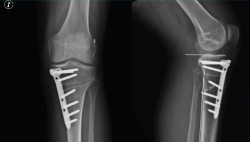

Figura 1. A: colocación del paciente con rodilla a 90° de flexión. Se marca la incisión de aproximadamente 4-6 cm que servirá para la extracción de los isquiotibiales y la osteotomía tibial alta; B: extracción de isquiotibiales para realizar la plastia.

Se marca sobre la piel la línea de incisión de 4-6 cm en la cara medial de la tibia proximal, aproximadamente 1,5 a 2 cm por debajo de la interlínea articular (Figura 1A). Una de las ventajas de esta osteotomía es que no precisa disecar e inestabilizar el ligamento colateral medial (LCM). El corte se realiza entre las dos inserciones del LCM y la placa se coloca por encima de este ligamento. De esta manera, la rodilla sigue estable aunque se decida realizar una retirada de la placa una vez consolidada la osteotomía.

Figura 4. Colocación de escoplos de forma progresiva para realizar la apertura (una vez realizados los cortes con la sierra).

Una vez hecho el túnel tibial, se introduce la plastia y se fija a nivel femoral y tibial (Figura 7). Si se utiliza una plastia de isquiotibiales, los autores recomiendan una fijación femoral cortical de suspensión regulable, dejando unos milímetros para el ajuste final después de la colocación de la placa de osteotomía. Una vez fijada la plastia, se procede a la colocación de la placa de osteotomía TomoFix® (Synthes, Oberdorf, Switzerland) para la tibia proximal medial (Figura 8). En la mayoría de los casos el tornillo más anterior coincide con el túnel tibial de RLCA, motivo por cual no se coloca (Figura 9).

Figura 9. Fijación de la placa con tornillos. Se señala con la flecha la ausencia del tornillo más anterior, dada su coincidencia con el túnel tibial.

Figura 10. Radiografía de control a los 3 meses en proyecciones anteroposterior y lateral. En la proyección lateral se aprecia que no se modifica la pendiente tibial posterior tras la osteotomía tibial alta de apertura medial.